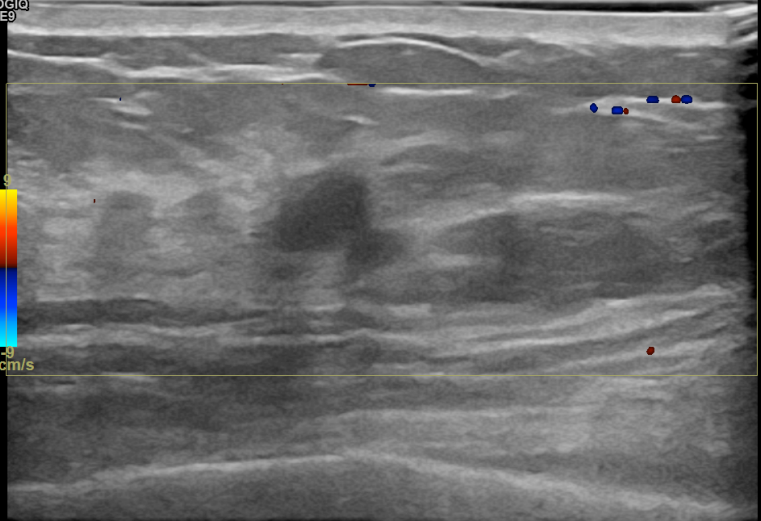

상기환자는 외부검사이상소견으로 조직검사위해 내원하신 40대후반

여성분으로 의심스러운 우측혹 조직검사 시행해 침윤성암 으로 진단되었습니다